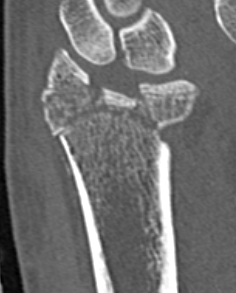

Unacceptable reduction

1.  Distal radial Step > 2mm

- leads to RC OA radiographically

- not proven to lead to dysfunction

Distal Radius Fracture Articular Step Coronal CTDistal Radius Fracture Articular Step Sagittal CT